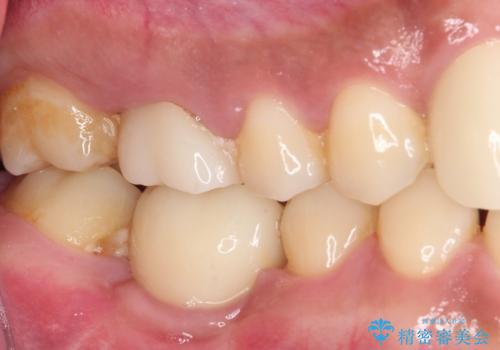

奥歯には元々欠損があり、欠損に伴う咬合不正も認められたため、部分矯正を行った上でインプラント補綴治療も行うこととしました。